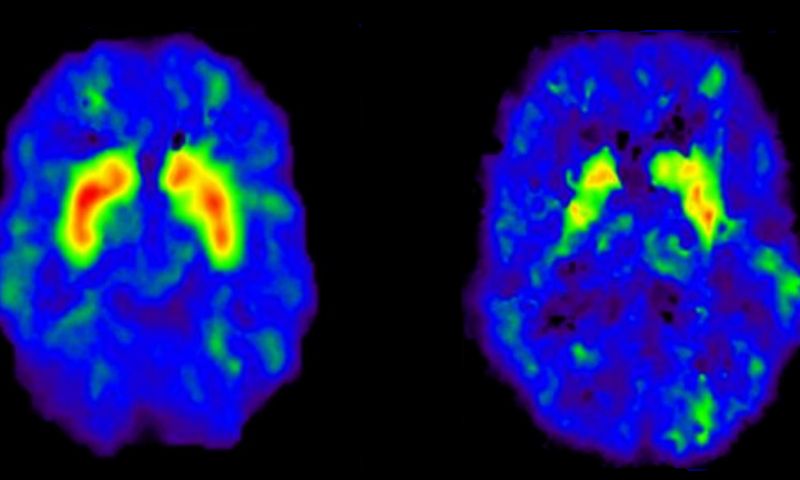

Al deze verschillende soorten informatie worden in verschillende delen van de hersenen verwerkt. Een door de onderzoekers ontwikkeld systeem, dat de gegevens van de fMRI-scanner analyseert met behulp van machine learning, kan vervolgens de algemene categorie herkennen van de zaken waaraan de proefpersonen denken.